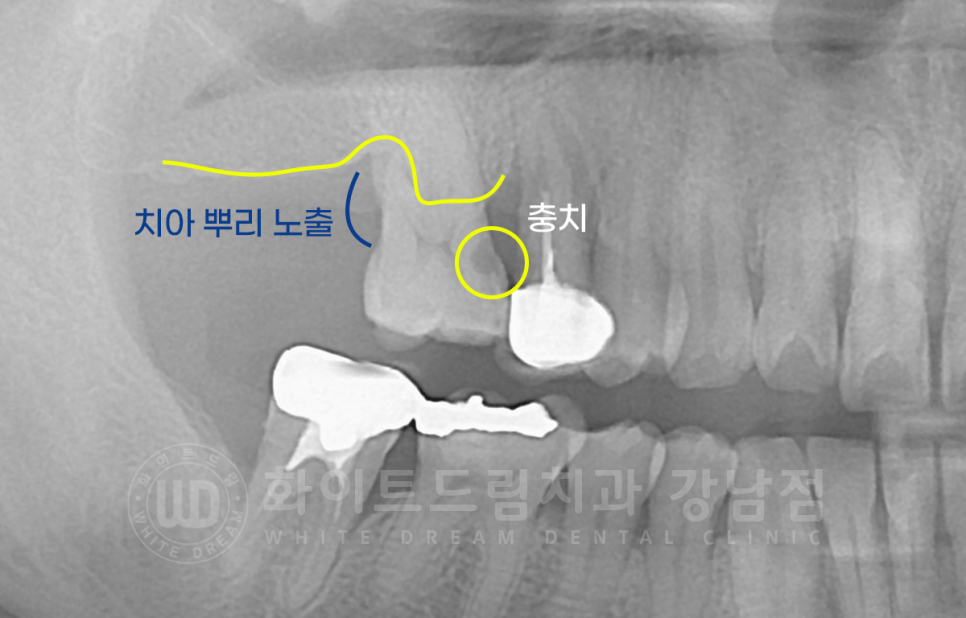

15번 치아는 염증으로 발치하지만, 16번은 왜 뽑았나요?

15번 치아는 크라운 치료를 받은 치아인데, 크라운 내부에 2차 충치가 발생했고

이로 인해 16번 치아에도 충치가 전염된 상태였습니다.

신경치료를 진행하고 사용하기에는 충치의 범위가 컸고, 염증으로 뿌리 한쪽이 이미 겉으로 드러나 있는 상태였기에

해당 치아도 발치를 진행했답니다.

서초동 어금니 임플란트 / 발치된 10번대 치아